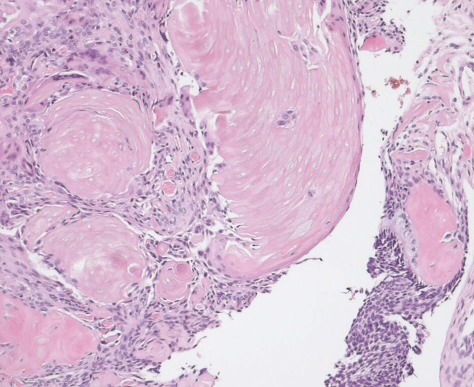

Ghost Cells

These cells have no nucleus, their outs de is visible, a nucleus and cytoplasm that cant b stained, and have had a loss of hemogloblin.

Common diseases/conditions are cystic odontogenic tumors, craniopharyngimas, and pilomatrcomas. .